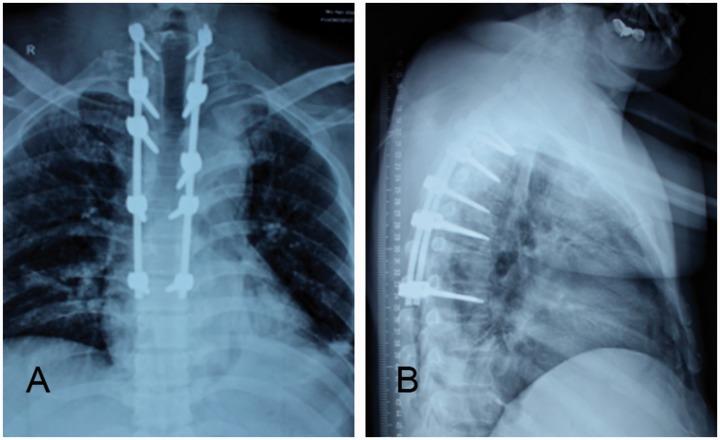

Rosai-Dorfman disease (RDD) or sinus histiocytosis with massive lymphadenopathy is a rare benign disorder usually characterized by massive painless cervical lymphadenopathy and systemic manifestations. Extranodal involvement, especially spinal involvement, is extremely rare. We report a 41-year-old man who presented with only intermittent dorsodynia. His condition was diagnosed as non-specific inflammatory disease on the basis of preoperative puncture biopsy results. We performed total surgical resection. Histopathological findings showed distinctive emperipolesis and immunohistochemistry results were positive for cluster of differentiation CD68 and S100 and negative for CD1a. A good prognosis was confirmed at the 3-month follow-up visit. This is the first case of RDD of the subdural spine with such a long segment lesion. There is still no consensus regarding appropriate therapy for this type of RDD and the preoperative diagnosis remains challenging. The unusual presentation of our case serves as a reference when diagnosing and treating RDD.

罗萨伊-多夫曼病(RDD)或伴有巨大淋巴结病的窦性组织细胞增生症是一种罕见的良性疾病,通常表现为无痛性巨大颈部淋巴结病和全身症状。结外受累,尤其是脊柱受累极为罕见。我们报告一名41岁男性,仅表现为间歇性背痛。根据术前穿刺活检结果,其病情被诊断为非特异性炎症性疾病。我们进行了全手术切除。组织病理学检查结果显示有独特的血细胞吞噬现象,免疫组化结果显示分化簇CD68和S100呈阳性,CD1a呈阴性。在3个月的随访中证实预后良好。这是首例硬膜下脊柱RDD伴如此长节段病变的病例。对于这类RDD的适当治疗仍未达成共识,术前诊断仍然具有挑战性。我们病例的不寻常表现为RDD的诊断和治疗提供了参考。